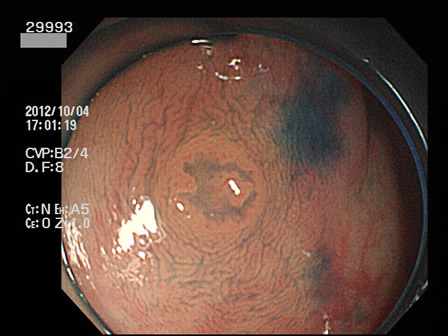

29901 29904 29905 29906 29907 29908 29909 29913 29915 29917 29918 29921 29925 29926 29927 29928 29930 29934 29936 29938 29939 29940 29941 29942 29943 29944 29945 29947 29948 29949 29955 29959 29961 29962 29965 29968 29972 29975 29979 29980 29981 29983 29985 29986 29987 29989 29993 29996 29998 29999・・・・・・・の50名

上記100名より抽出した平坦・陥凹型腺腫(=癌化の危険が高いが見落としやすい病変)の内視鏡写真